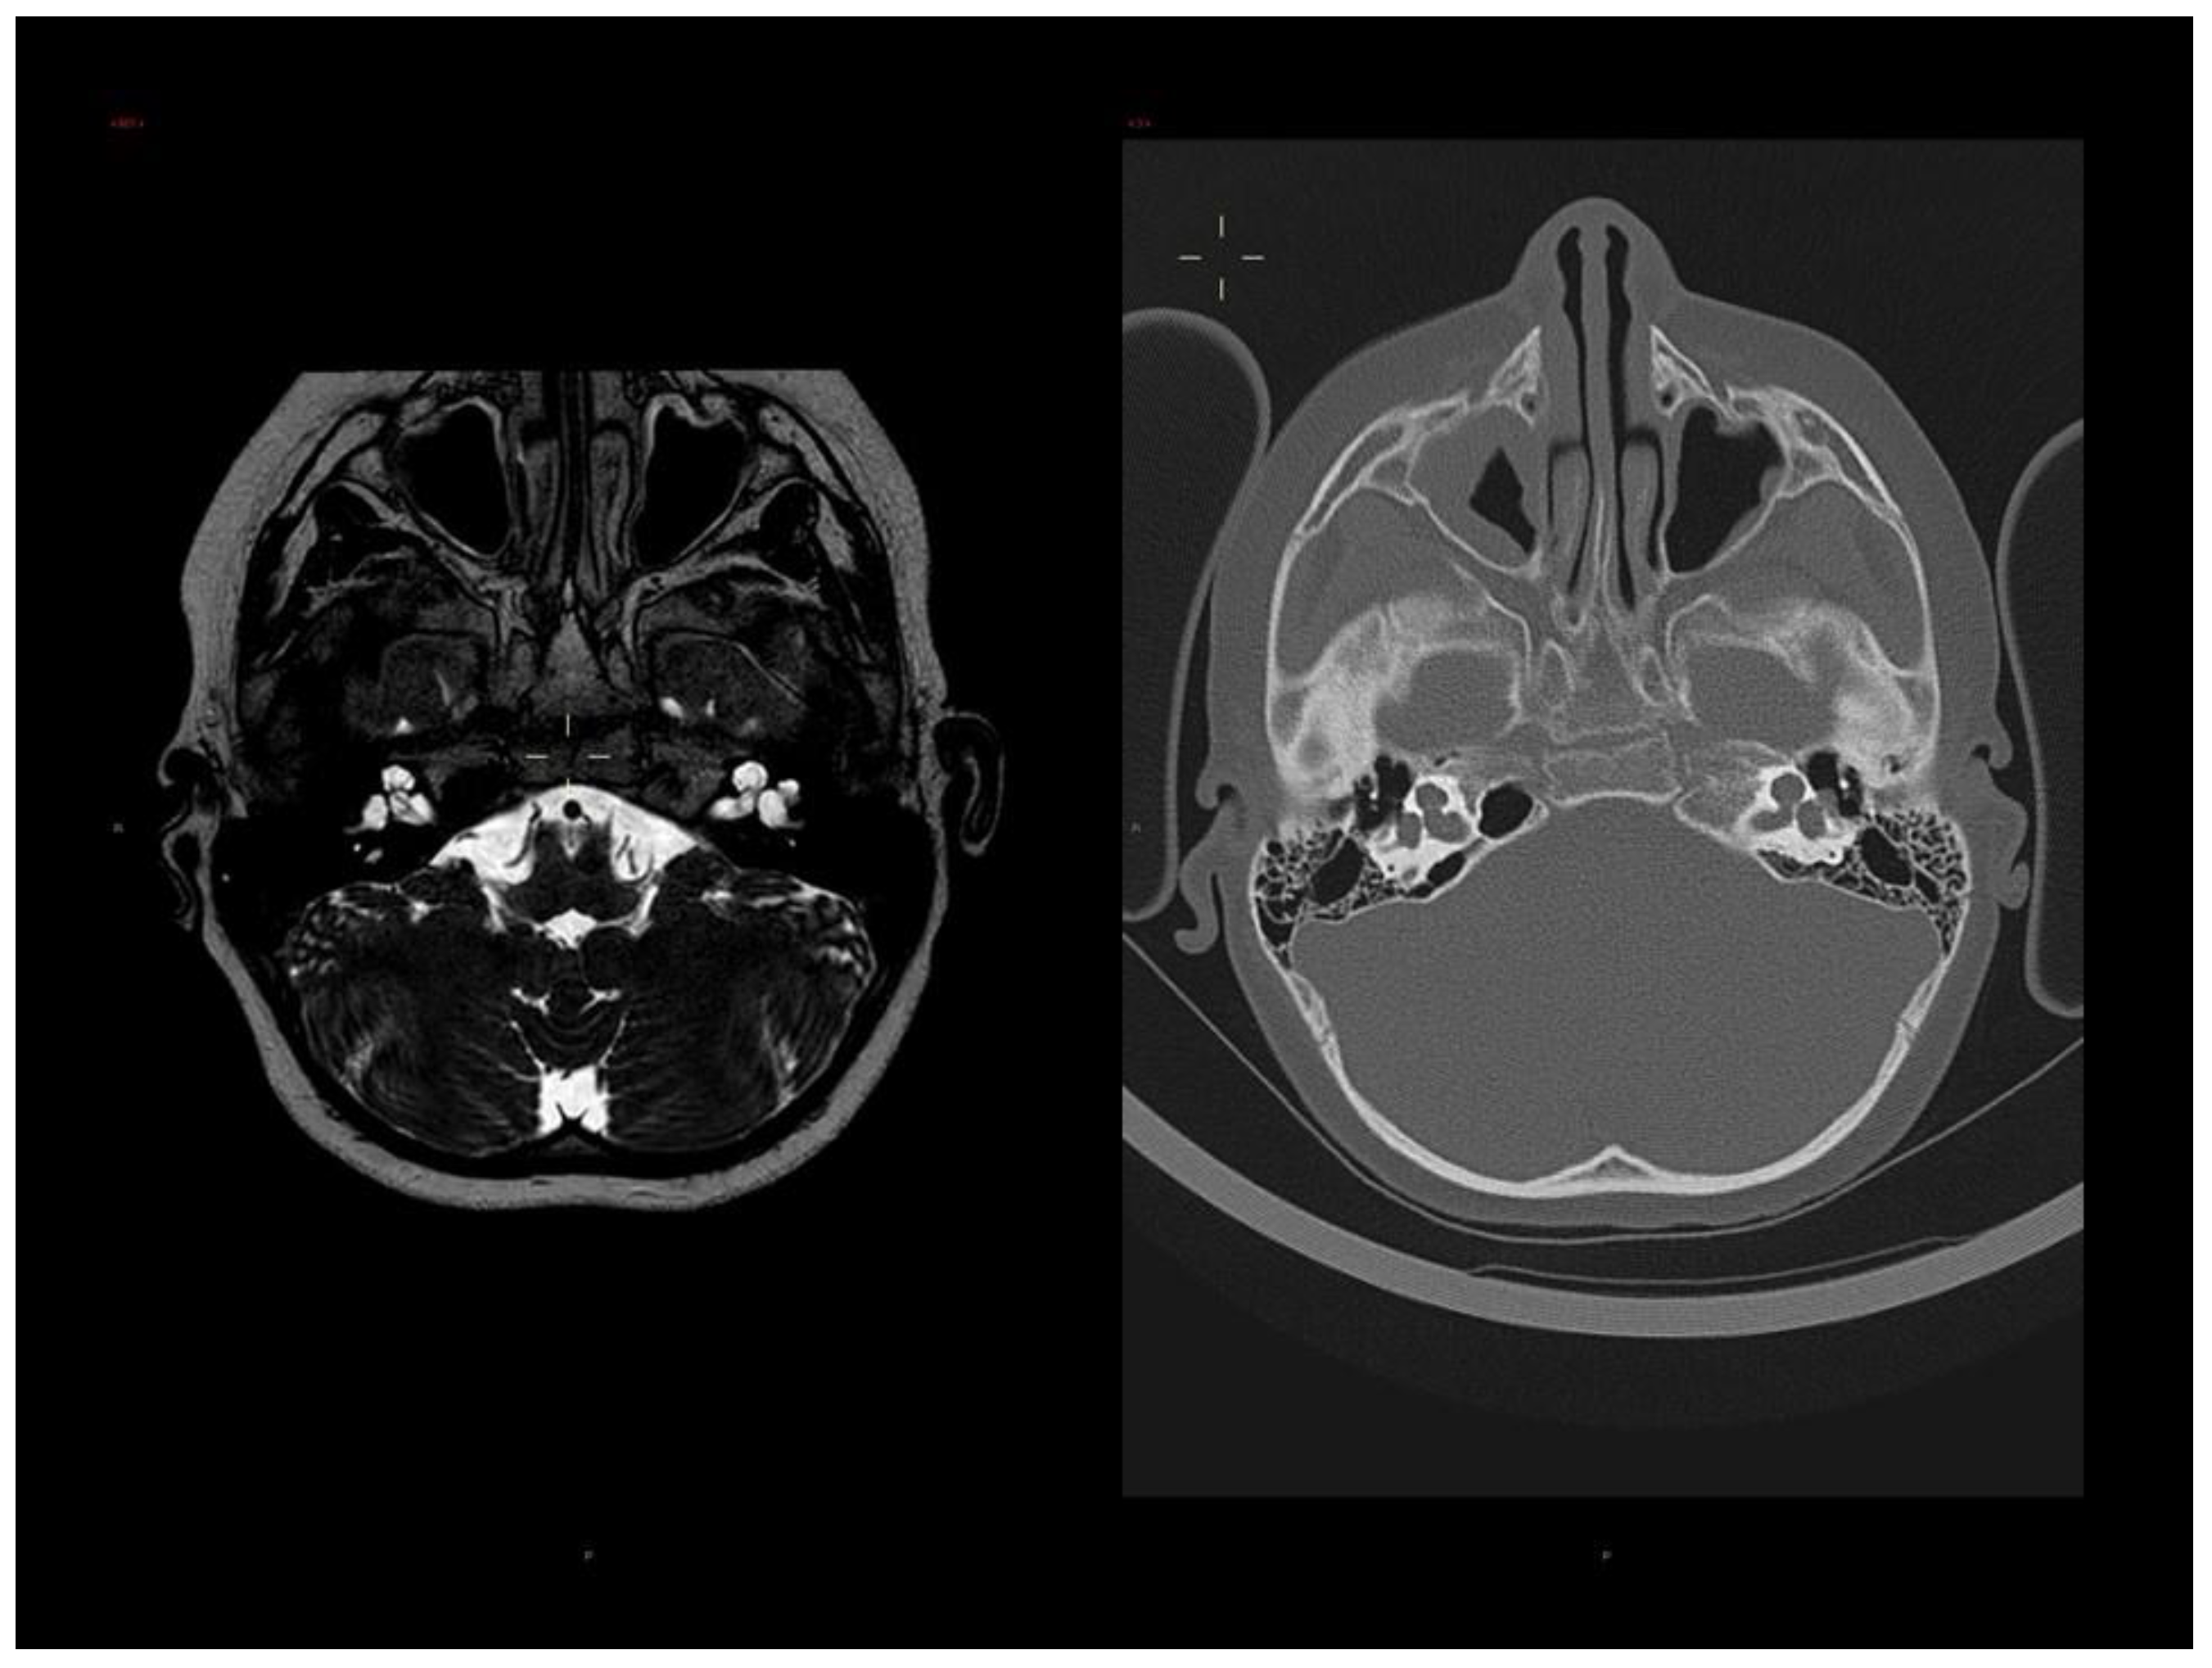

3.1. Clinical Report